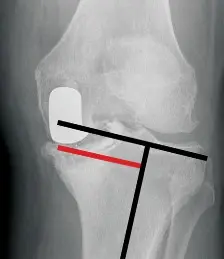

- الأشعة السينية (X-rays): تُعد الأشعة السينية القياسية (الأمامية الخلفية والجانبية) ذات الجودة العالية حجر الزاوية في تشخيص عيوب العظام. تظهر هذه الصور طبيعة وحجم العيوب العظمية بدقة، وتساعد في تحديد ما إذا كانت العيوب محتواة (contained) داخل العظم أو غير محتواة (noncontained).

- شكل التعويض الساقي: يدرس الجراح ما إذا كان التعويض الساقي يجب أن يكون مسطحاً (يوزع القوة بالتوازي مع خط المفصل) أو وتدياً (يحافظ على المزيد من العظم).

* التعويضات الموضوعة على السطح البعيد تقلل من فجوة البسط، بينما تلك الموضوعة خلفياً تقلل من فجوة الثني.